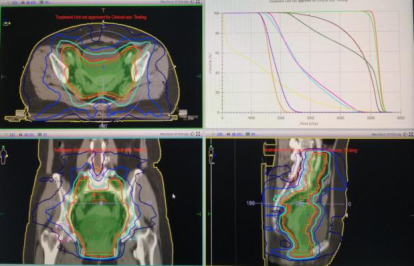

放疗:盆腔IMRT DT50.4Gy/28f,后装A点剂量DT24Gy/4f

第一阶段治疗